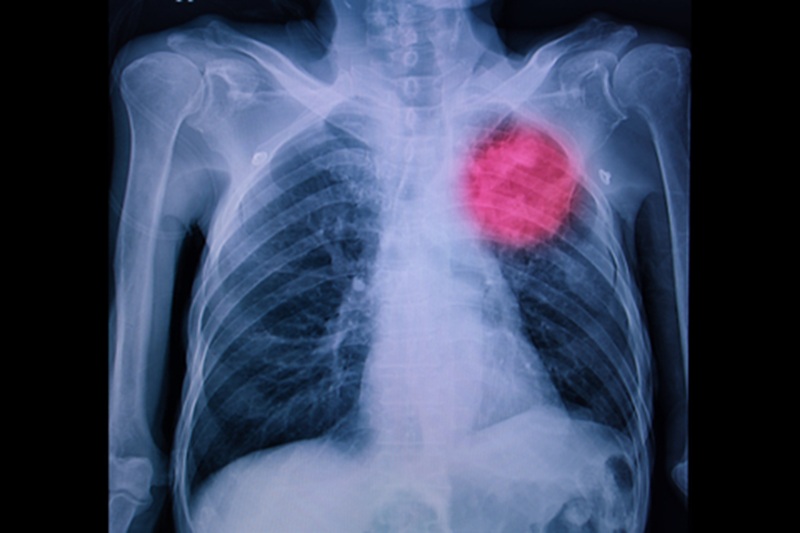

Путем аппаратного мониторинга специалистам удается изучать легкие, другие органы грудной полости и выявлять у пациентов своевременно различные нарушения. С помощью теней, запечатленных на снимках рентгена, врачи могут анализировать состояние легких и давать профессиональные заключения, назначать лечение, давать рекомендации.

По окончании диагностики очертания, интенсивности, распространенности теней специалисты способны выявлять:

- воспалительные процессы в плевре, тканях легких, бронхах;

- наличие у человека туберкулеза;

- обнаружить эмфизему;

- злокачественные опухоли;

- выявить отек легких;

- ателектаз;

- кардиальную, сосудистую патологии;

- распознать трещины, переломы ребер;

- наличие в плевральной полости нетипичной для нее жидкости;

- пневмоторакс и другие заболевания, состояния.